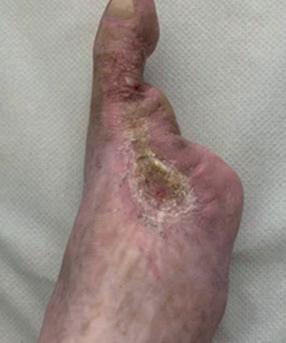

Left: Pre- and postoperative images (courtesy of Dittmar Böckler) of the first European implantation of the Gore Tag TBE; above: Dittmar Böckler performing the implantation